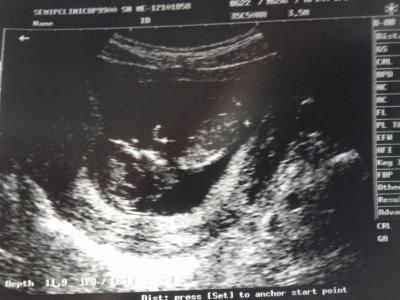

Hallo Ihr Lieben, vielen vielen Dank fürs Daumen drücken. Hat geholfen!!!! Unserem Krümmel geht es sehr gut. Er ist schon 6 cm gross und hat kräftig gestrampelt und geboxt :). Habe heute auch endlich mal ein Bild für Euch :-). LG von der überglücklichen Nula

Freut mich das alles in Ordnung ist :) Schönes Bildchen hast du Lg Susi